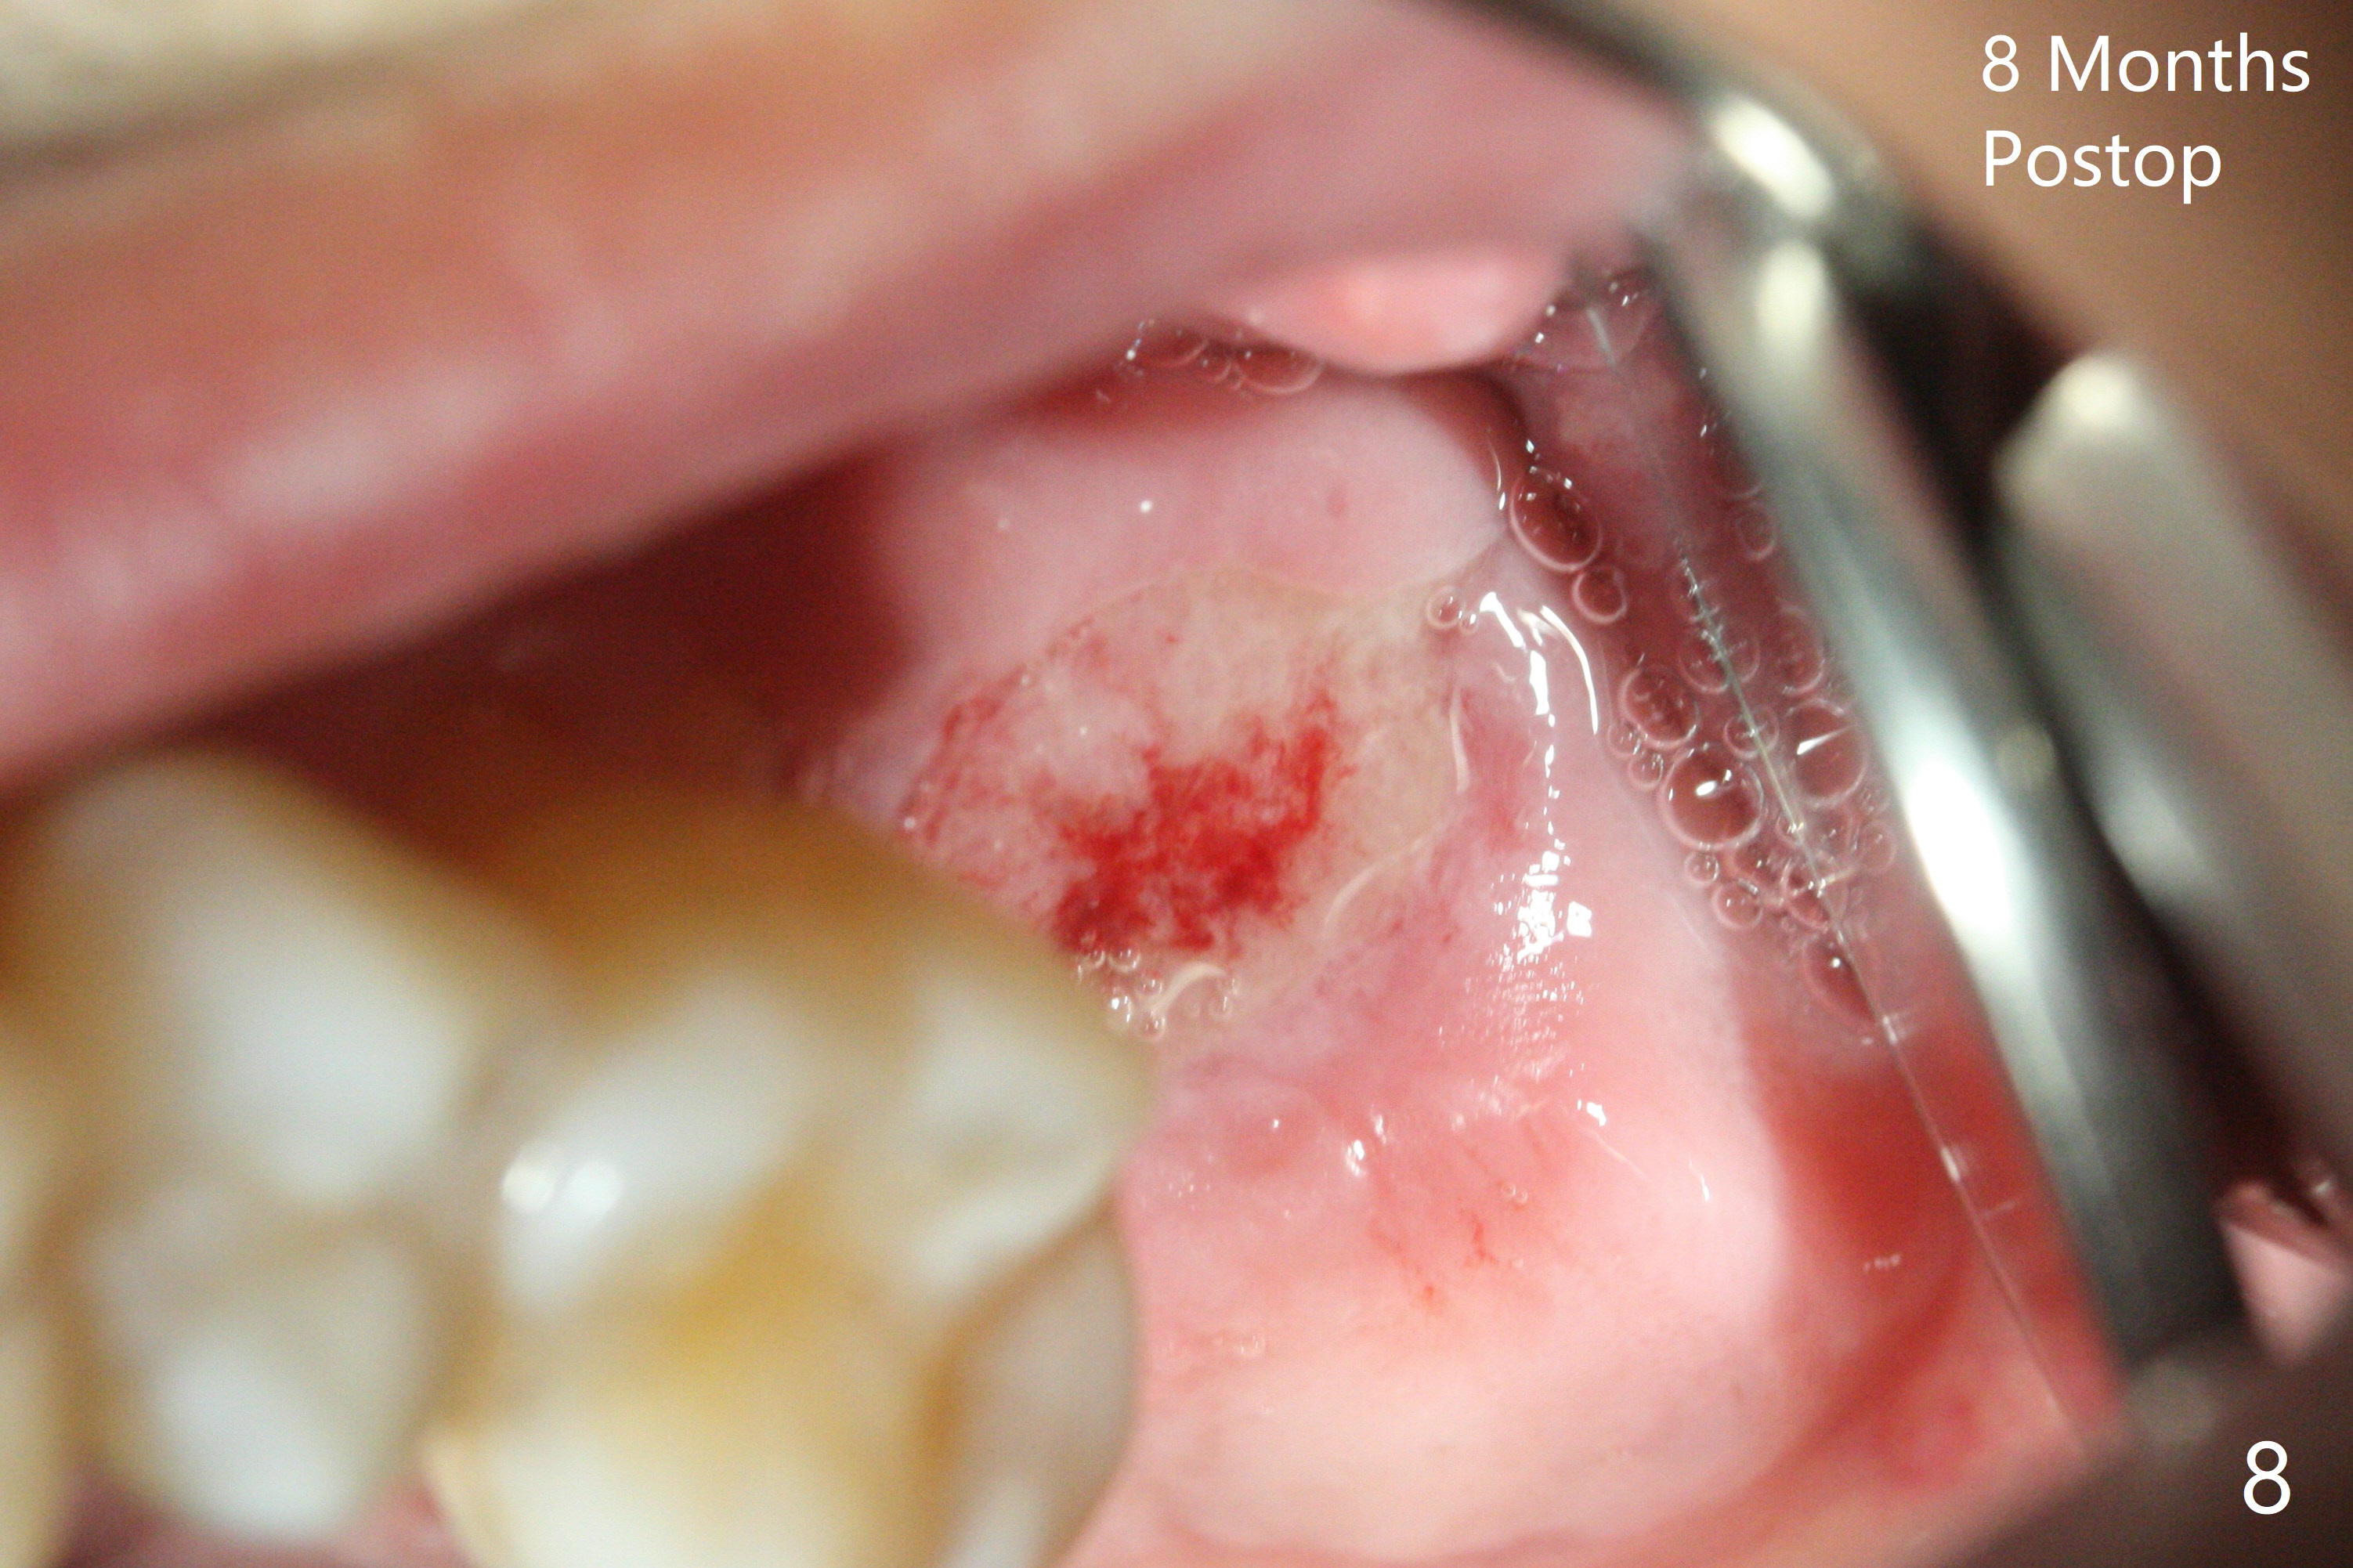

After 4.5x7.3 mm drill with 3 O-rings at #15, use 2.2x7.3 mm one with 2 O-rings. The sinus floor feels like to be perforated, but perio probe does not find the perforation. Nose blowing does not reveal air leakage. It seems fine when 3.0x7.3 mm one with 2 O-rings is being used. The sinus membrane perforates when Magic Sinus Lifter is used. Mixture of autogenous bone (from drills) and allograft does not stick to the periosteal elevator (Fig.1). Forty-minute centrifuge leads to separation of serum (Fig.2 S) from Red Blood Cell layer (R). The separation of the top tube is incomplete with RBC invade the serum layer in a few second (Fig.3 arrow). While the serum layer of the bottom tube is prepared for PRF membrane, a part of the serum layer of the top tube is withdrawn to make sticky bone (Fig.4). The top tube returns to the centrifuge for another 30 minutes to make the second PRF membrane. The first PRF membrane is inserted into the osteotomy and pushed into the sinus with empty feeling, followed by the sticky bone and last by the 2nd PRF membrane. A 5x7.3 mm implant is placed with ~ 10 Ncm, followed by a 6.8x4 mm healing abutment (Fig.5,6 (retrospectively healing screw should be used to reduce sinus-oral communication)). There is no mushroom in the sinus, but hopefully the sticky bone will stick to the bottom of the sinus for maturation. Sinus surgery precaution is provided. Next time tap or dummy implant will be used for sinus lift after initial osteotomy with guide. In fact the patient with diabetes under control has mild cold. The procedure should have been canceled. There is no postop nasal hemorrhage or discharge. The patient returns nearly 8 months postop. The wound is infected. The healing abutment is changed to a healing screw with oral antibiotic. Two weeks later, the area remains infected with symptoms (Fig.7-9). The healing screw is not covered completely. After implant removal, the sinus membrane is perforated. A piece of collagen plug (preferably Osteogen plug) is inserted (Fig.10,11). Because of the concavity, bone graft seems necessary when the wound heals. One week later, perimplantitis develops at #2. The patient is ready for the 3rd placement 1 year 5 months post last implant removal (Fig.12). The bone is 1.8 mm thick, apparently composing of 2 fused cortical plates. Make an incision for both external and internal sinus lift with retraction. Find the old guide to start osteotomy including bone trimmers and use Magic Lifter. If the membrane is broken, open the lateral window to repair with PRF.